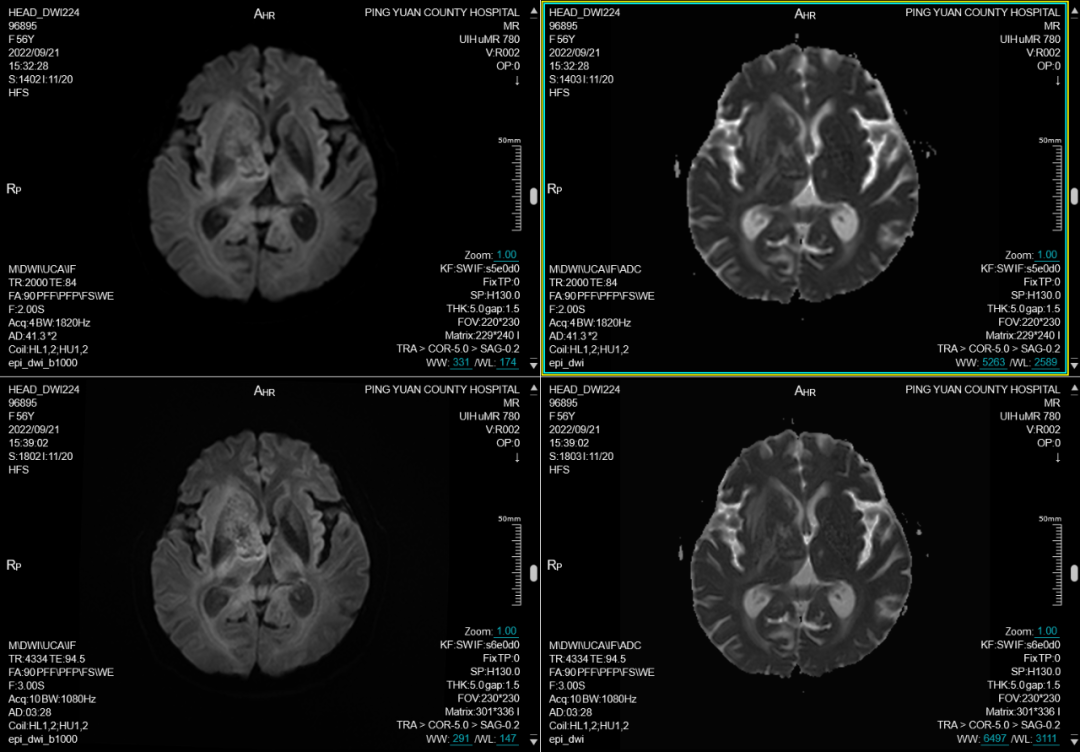

二、弥散加权成像技术(DWI): 弥散加权成像(DWI)是唯一活体检测水分子扩散运动的方法,这项技术应用成熟,可准确判断脑卒中分期,有助于脑肿瘤的诊断及鉴别诊断;随着技术的进展,DWI已经在乳腺、肝脏、子宫附件、前列腺及脊柱骨骼等其它领域得到广泛应用。

联影磁共振怎么样平原县第一人民医院联影uMR780 光梭3.0T磁共振正式投入使用,开启医学影像新时代!_https://www.jmylbn.com_新闻资讯_第7张